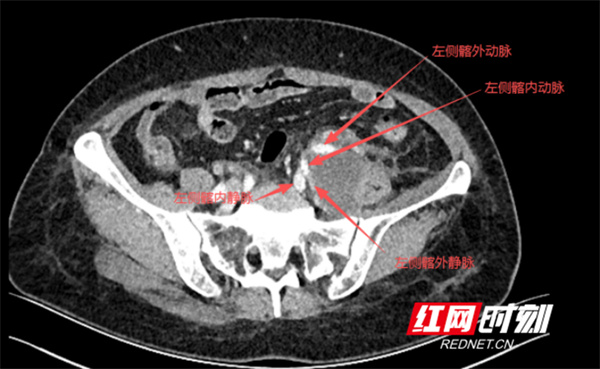

入院后,医院为黄女士完善肿瘤标志物、胸腹部CT平扫+增强、腹部MRI平扫+增强、PET-CT等全面检查,明确其腹膜后肿瘤已包埋压迫左侧髂内动静脉及左侧输尿管,手术难度极大,术中极易损伤大血管引发大出血,危及生命。为此,该院胃肠外科立即启动多学科诊疗(MDT)会议,联合肿瘤科、血管外科、泌尿外科、麻醉科、重症医学科、医学影像科及病理科专家共同会诊。

专家们一致认为,该肿瘤紧贴并包埋压迫左侧髂内外动静脉,且术前无法明确肿瘤性质,若要实现根治性切除,术中大出血风险极高。鉴于病情棘手,胃肠外科副主任结合其在西京医院的学习经历,提出邀请腹膜后肿瘤切除经验丰富的西京医院岳树强教授指导手术。经与患者及家属充分沟通,最终决定由岳树强教授主导手术。

患者CT影像上可见肿瘤侵犯压迫多处大血管。

手术如期开展,打开腹腔分离肿瘤与周围组织后,术中所见与术前预判完全一致:肿瘤已侵犯并压迫左侧腹腔多处大血管及左侧输尿管。最惊心动魄的环节的是分离肿瘤与腹主动脉、左侧髂总动脉、髂内外动静脉之际——肿瘤组织如水泥般紧紧“黏附”在血管外膜,无明确分离间隙。岳树强教授与胃肠外科专科主任曾之耀带领手术团队,凭借丰富的临床经验、对解剖层次的深刻把握及精湛的手术技巧,成功将肿瘤完整切除。